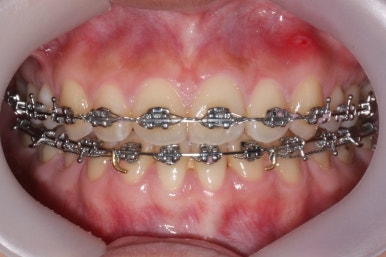

장치를 부착하였습니다.

부산교정전문의 키다리아저씨치과에서 이번에 사용한 장치는 메탈장치이며, 가장 기본적이고 역사가 오래된 장치가 되겠습니다.

이제 치료가 끝났습니다.

매우 치아가 가지런해졌고, 당연히 덧니는 해소가 되었으며 맞물림도 굉장히 좋아졌습니다.

치아가 매우 가지런해졌고, 덧니도 개선이 되었습니다.

맞물림도 굉장히 좋아졌네요.